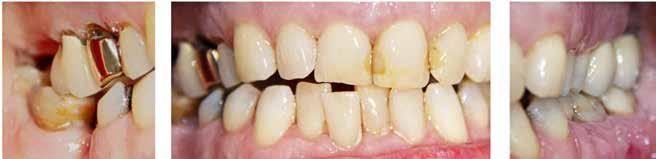

Fig. 2. Med udgangspunkt i tænder med stigende sammenbrud af en dentineksponeret carieslæsion kan et forventeligt billede af et fremadskridende mønster af ubehandlet caries fremstilles. Jo flere sammenbrudte dentinflader, desto mere åbenlæsions-topologi (A-E). I forhold til radiologisk penetrationsdybde tæt på pulpa vil dybdelæsioner med synlig radioopak zone mellem læsion og pulpa have lav risiko for bakterier i pulpa (F) overfor ekstremt dybe læsioner, der har radiologisk kontakt til pulpa (G). Læsionens topologi har konsekvenser for vækstbetingelserne af en biofilm. ”Lukkede” dentin-caries-læsioner har tydelig biofilmakkumulering, blød gullig/lysbrun dentinoverflade og med et underminerende spredningsmønster langs med emalje-dentin-grænsen (H). I modsætning til ”åbne” læsioner, der er mere mørkfarvede uden nævneværdig akkumulering af biofilm (I). (Med tilladelse fra (16) og Wiley).

Fig. 2. A picture of a progressing pattern of one untreated caries lesion is expected based on teeth with increasing break-down of a dentine-exposed carious lesion, and this is confirmed in this figure. The more surfaces that are involved in a cavity the more “open” topology (A-E). In relation to the radiological penetration depth close to the pulp, deep lesions with a visible radiopaque zone between the lesion and the pulp will have a low risk of bacteria in the pulp (F) compared to extremely deep lesions that have radiological contact with the pulp (G). The topology of the lesion has consequences for the growth conditions of a biofilm. "Closed" dentin caries lesions have clear signs of biofilm accumulation, a soft yellowish/light brown dentin surface and with an undermining spreading pattern along the enamel-dentine border (H). In contrast to “open” lesions that are darker in colour without appreciable accumulation of biofilm (I). (With permission from (16) and Wiley).

filmen, og deres produktion af organiske syrer fører til demineralisering af de hårde tandvæv (emalje, dentin og cement). I begyndelsen vil demineraliseringen ikke føre til en egentlig kavitetsdannelse på tandoverfladen til trods for, at der både er mineraltab i emalje og dentin, men den gradvise demineralisering over tid vil ubehandlet kunne svække emaljelæsionens centrale dele. De mastikatoriske kræfter vil føre til dannelse af mikrokaviteter efterfulgt af egentlige kliniske kaviteter (Fig. 1). På sigt fører dette til, at den demineraliserede emaljelæsion bryder sammen og eksponerer den underliggende demineraliserede dentin. På dette tidspunkt siges læsionen at være kaviteret eller klinisk dentin-eksponeret. Hvorvidt en carieslæsion progredierer eller ej, beskrives konceptuelt med begrebet “cariesaktivitet” eller “læsionsaktivitet”. Begrebet dækker både over, hvorvidt der ses akkumulering af biofilm på overfladen af carieslæsionen, samt hvorvidt man klinisk kan se tegn på aktiv produktion af syre i den akkumulerede biofilm. Cariesaktivitet kan tillige bekræftes radiologisk (Fig. 1A og B). En aktiv carieslæsion er kort sagt dækket af en cariogen biofilm og vil derfor progrediere med øget penetrationsdybde af læsionen til følge, hvorimod en inaktiv carieslæsion ikke på samme måde har en overfladebiofilm og heller ikke vil udvikle sig med særlig stor hastighed (1). Om end inaktive carieslæsioner vil kunne aktiveres på ny, er den nuværende kliniske forståelse, at intervention ikke umiddelbart er nødvendigt eller i det mindste kan begrænses kraftigt i tilfælde af inaktive læsioner. Muligheden for akkumulering af biofilm, selv i en kaviteret carieslæsion, afhænger til en vis grad af, hvorvidt carieslæsionen kan beskrives som værende “lukket” eller “åben” (16). Jo færre tandflader der er involveret i en kaviteret carieslæsion, jo mere “lukket” eller “skålformet” vil læsionens topologi være (Fig. 2A-E), hvilket tillader akkumulering af biofilm i læsionsmiljøet. En carieslæsion med et lukket læsionsmiljø vil derfor som oftest være en aktiv læsion, hvorimod åbne carieslæsioner ikke vil kunne akkumulere biofilm i samme omfang og derfor vil forventes at have en tilsvarende lavere progressionshastighed til trods for et ellers fremskredent stadie. Aktive dentin-caries-læsioner dækket af biofilm vil klinisk kunne beskrives som værende hvidlige/gullige/lysbrune (Fig. 2H-I), og den carierede dentin vil være blød og ikke mindst fugtig eller våd. I modsætning hertil fremstår inaktive læsioner mørkfarvede, læderagtige og uden nævneværdig akkumulation af biofilm (Fig. 2I). Desuden udviser inaktive carieslæsioner ikke samme grad af fugtighed (22). Progression og spredning af en aktiv carieslæsion vil ikke blot føre til øget penetrationsdybde, men også lede til underminering af emaljen. Dette kan ses som retrograd demineralisering (Fig. 2H). I takt med at carieslæsionen gradvist underminerer emaljen, vil emaljen på et tidspunkt være så u-understøttet, at den almindelige tyggefunktion vil føre til, at emaljen knækker af. Et resultat af dette er, at carieslæsionen bliver mere “åben”. I den nu relativt mere åbne carieslæsion vil akkumulering af biofilm ikke kunne finde sted i samme omfang som før (Fig. 2I), og carieslæsionens progressionshastighed eller aktivitet vil mindskes eller stoppe fuldstændigt (16,23). Dette dynamiske skift imellem aktivitet og inaktivitet kan ses ved både dybe og mindre dybe carieslæsioner og danner fra et klinisk perspektiv